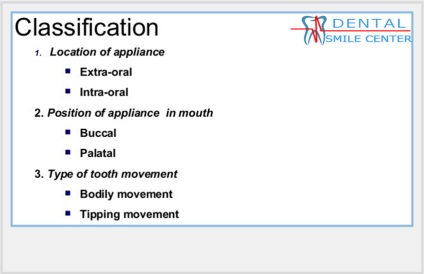

Distalization moláris - az az oldal csoport fogszabályozási mozgását a fogak (őrlőfogak) ezelőtt. Distalization őrlőfogak gyakran az első lépés a kezelésére különböző malocclusions eltávolítása nélkül a premolárisoknál vagy a kezelés a eltávolítása a második őrlőfogak. By eszközök distalization felső őrlő fogaknál levehető extra- és intraorális, például egy arc arc, a lemez csavarral és ágazati megszorítások, amelyek előírják jó együttműködés az orvos és a beteg nem eltávolítható eszközök.